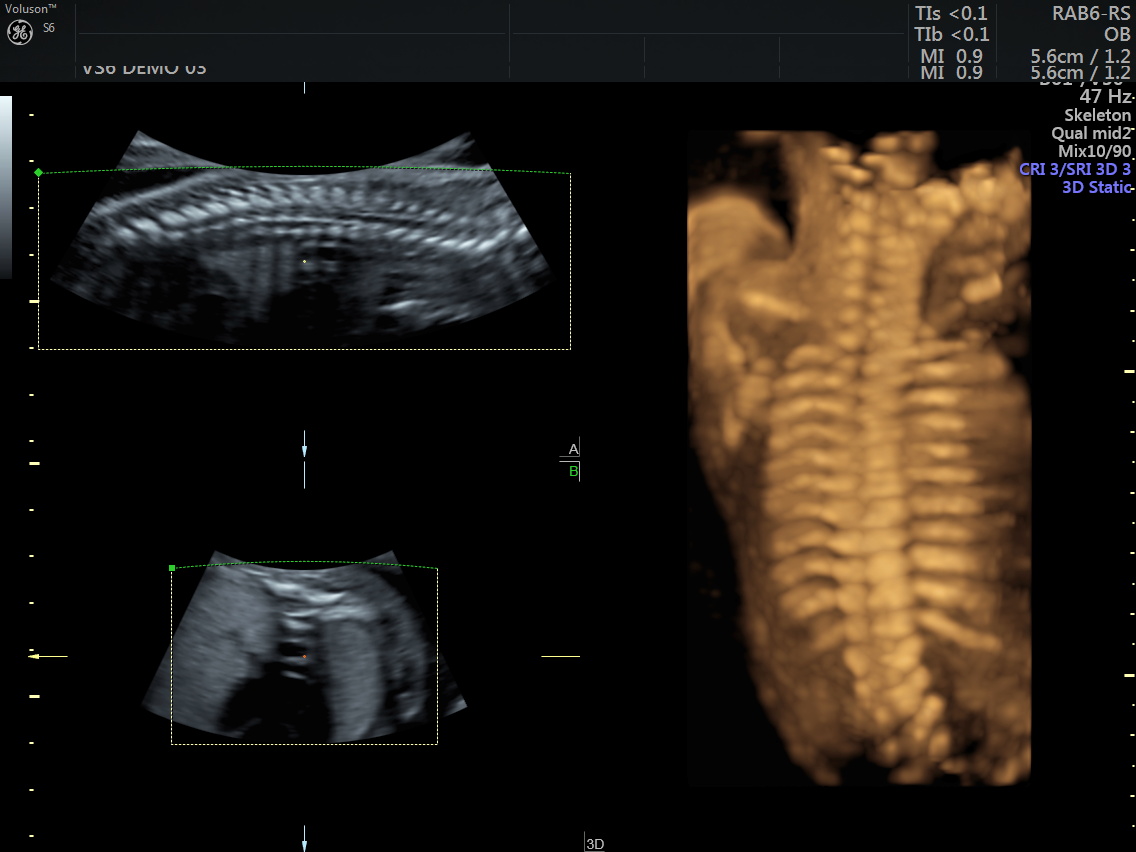

4 boyutlu renkli ultrason cihazı ile çok erken dönemde cinsiyet, yarık dudak, yarık damak, eksik parmak, beyin ve omurilikten kaynaklanan rahatsızlıkların erken tanısı konulabiliyor.